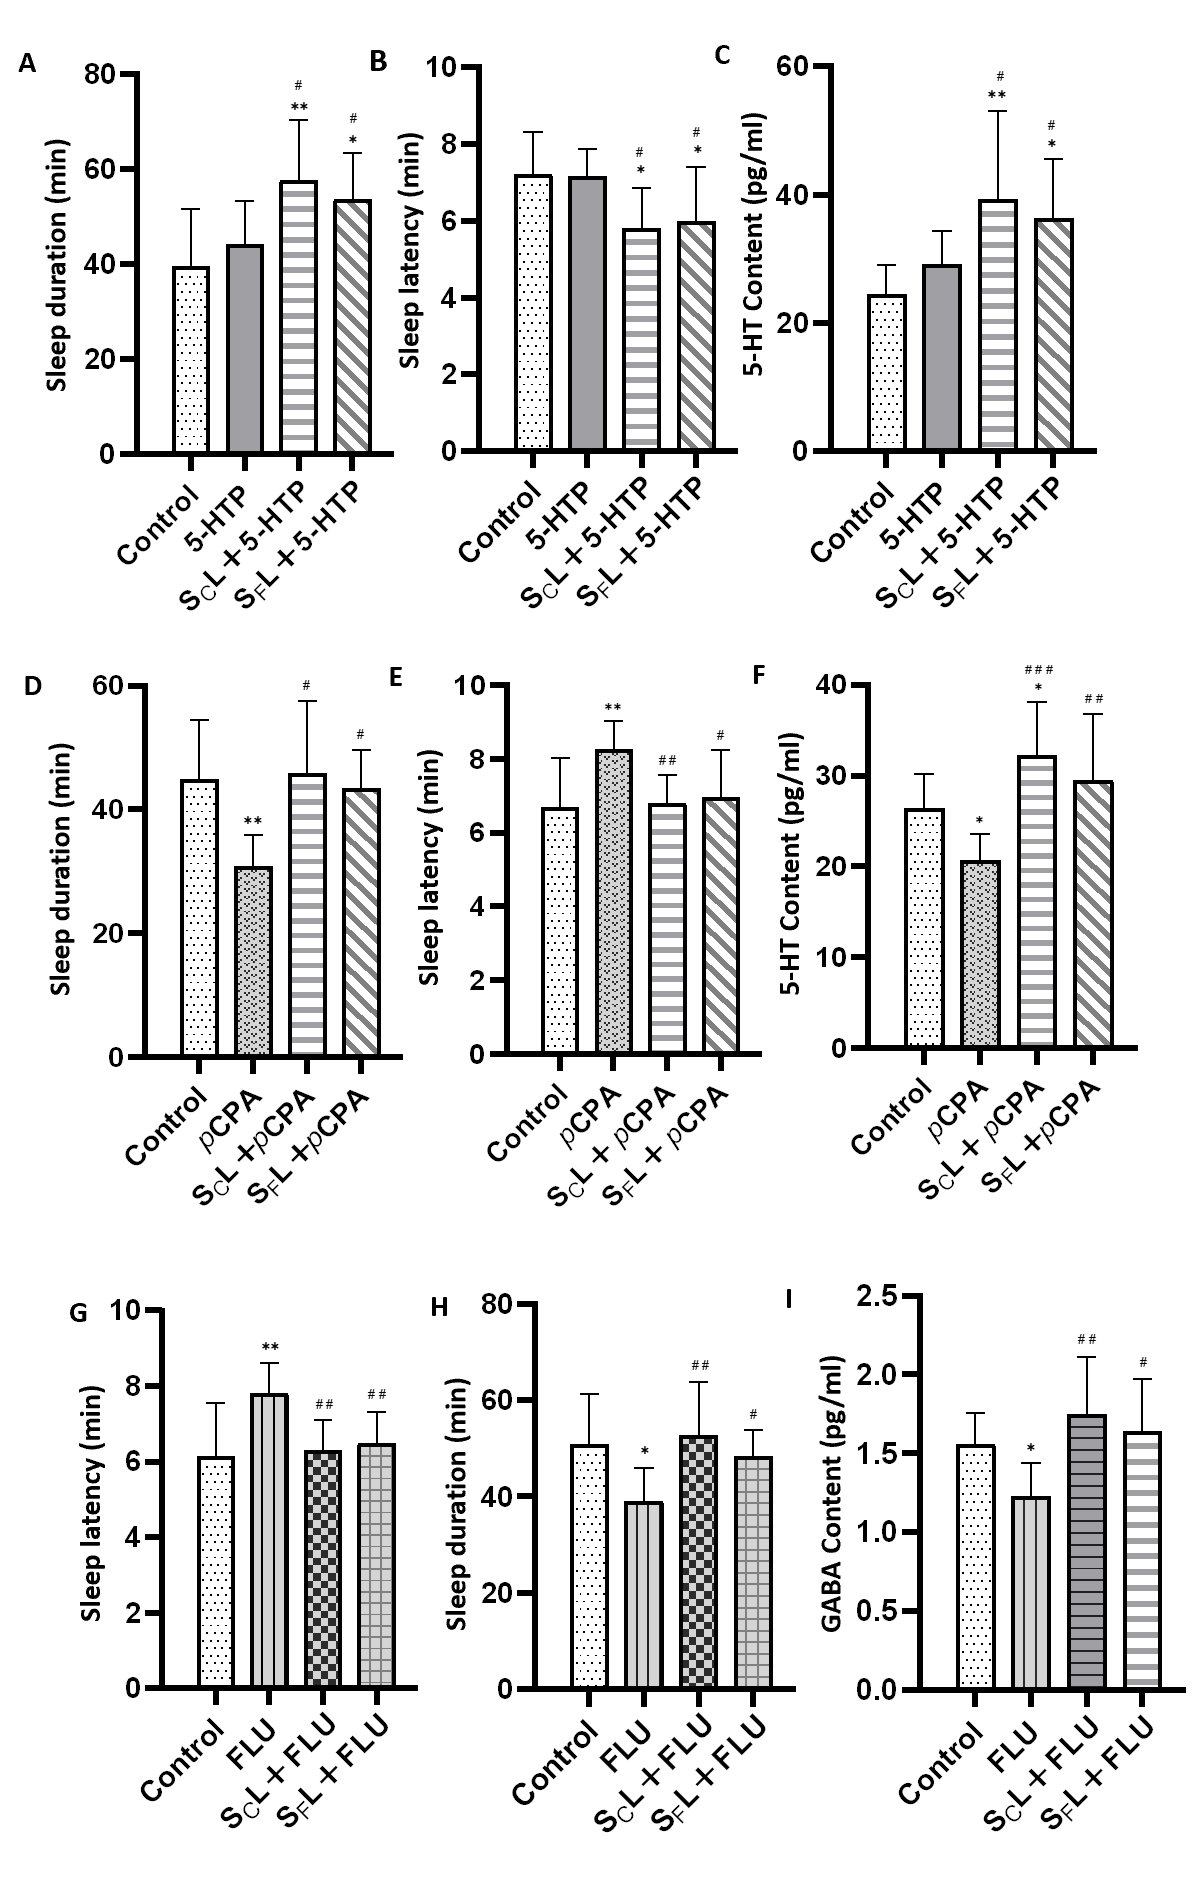

尽管SCL和SFL在民间长期用于改善失眠,但其镇静催眠作用缺乏系统研究支持。本研究通过自发活动实验、戊巴比妥钠诱导睡眠实验、对氯苯丙氨酸失眠模型实验及氟马西尼逆转催眠实验,综合评价了二者的镇静催眠活性。结果表明,SCL和SFL均以剂量依赖方式增强戊巴比妥的睡眠效应(图2)、改善氯苯丙氨酸(pCPA)所致的失眠状态(图3),且SCL的效果显著优于SFL。氟马西尼可抑制两者的催眠作用(图3),同时,SCL与SFL均与5-HTP表现出协同催眠效应(图3),表明5-HT与GABA系统共同介导其镇静催眠活性。

图3与5-HTP协同诱导睡眠时长(A)和潜伏期(B)及小鼠海马5-羟色胺含量(C),pCPA诱导失眠小鼠的睡眠持续时间(D)和潜伏期(E)及海马中5-HT含量(F),流感致失眠小鼠的睡眠潜伏期(G)和持续时间(H)与海马种GABA含量(I)(与对照组比较,*p< 0.05,**p< 0.01,***p< 0.001;与模型组比较,#p< 0.05,##p< 0.01,###p< 0.001)